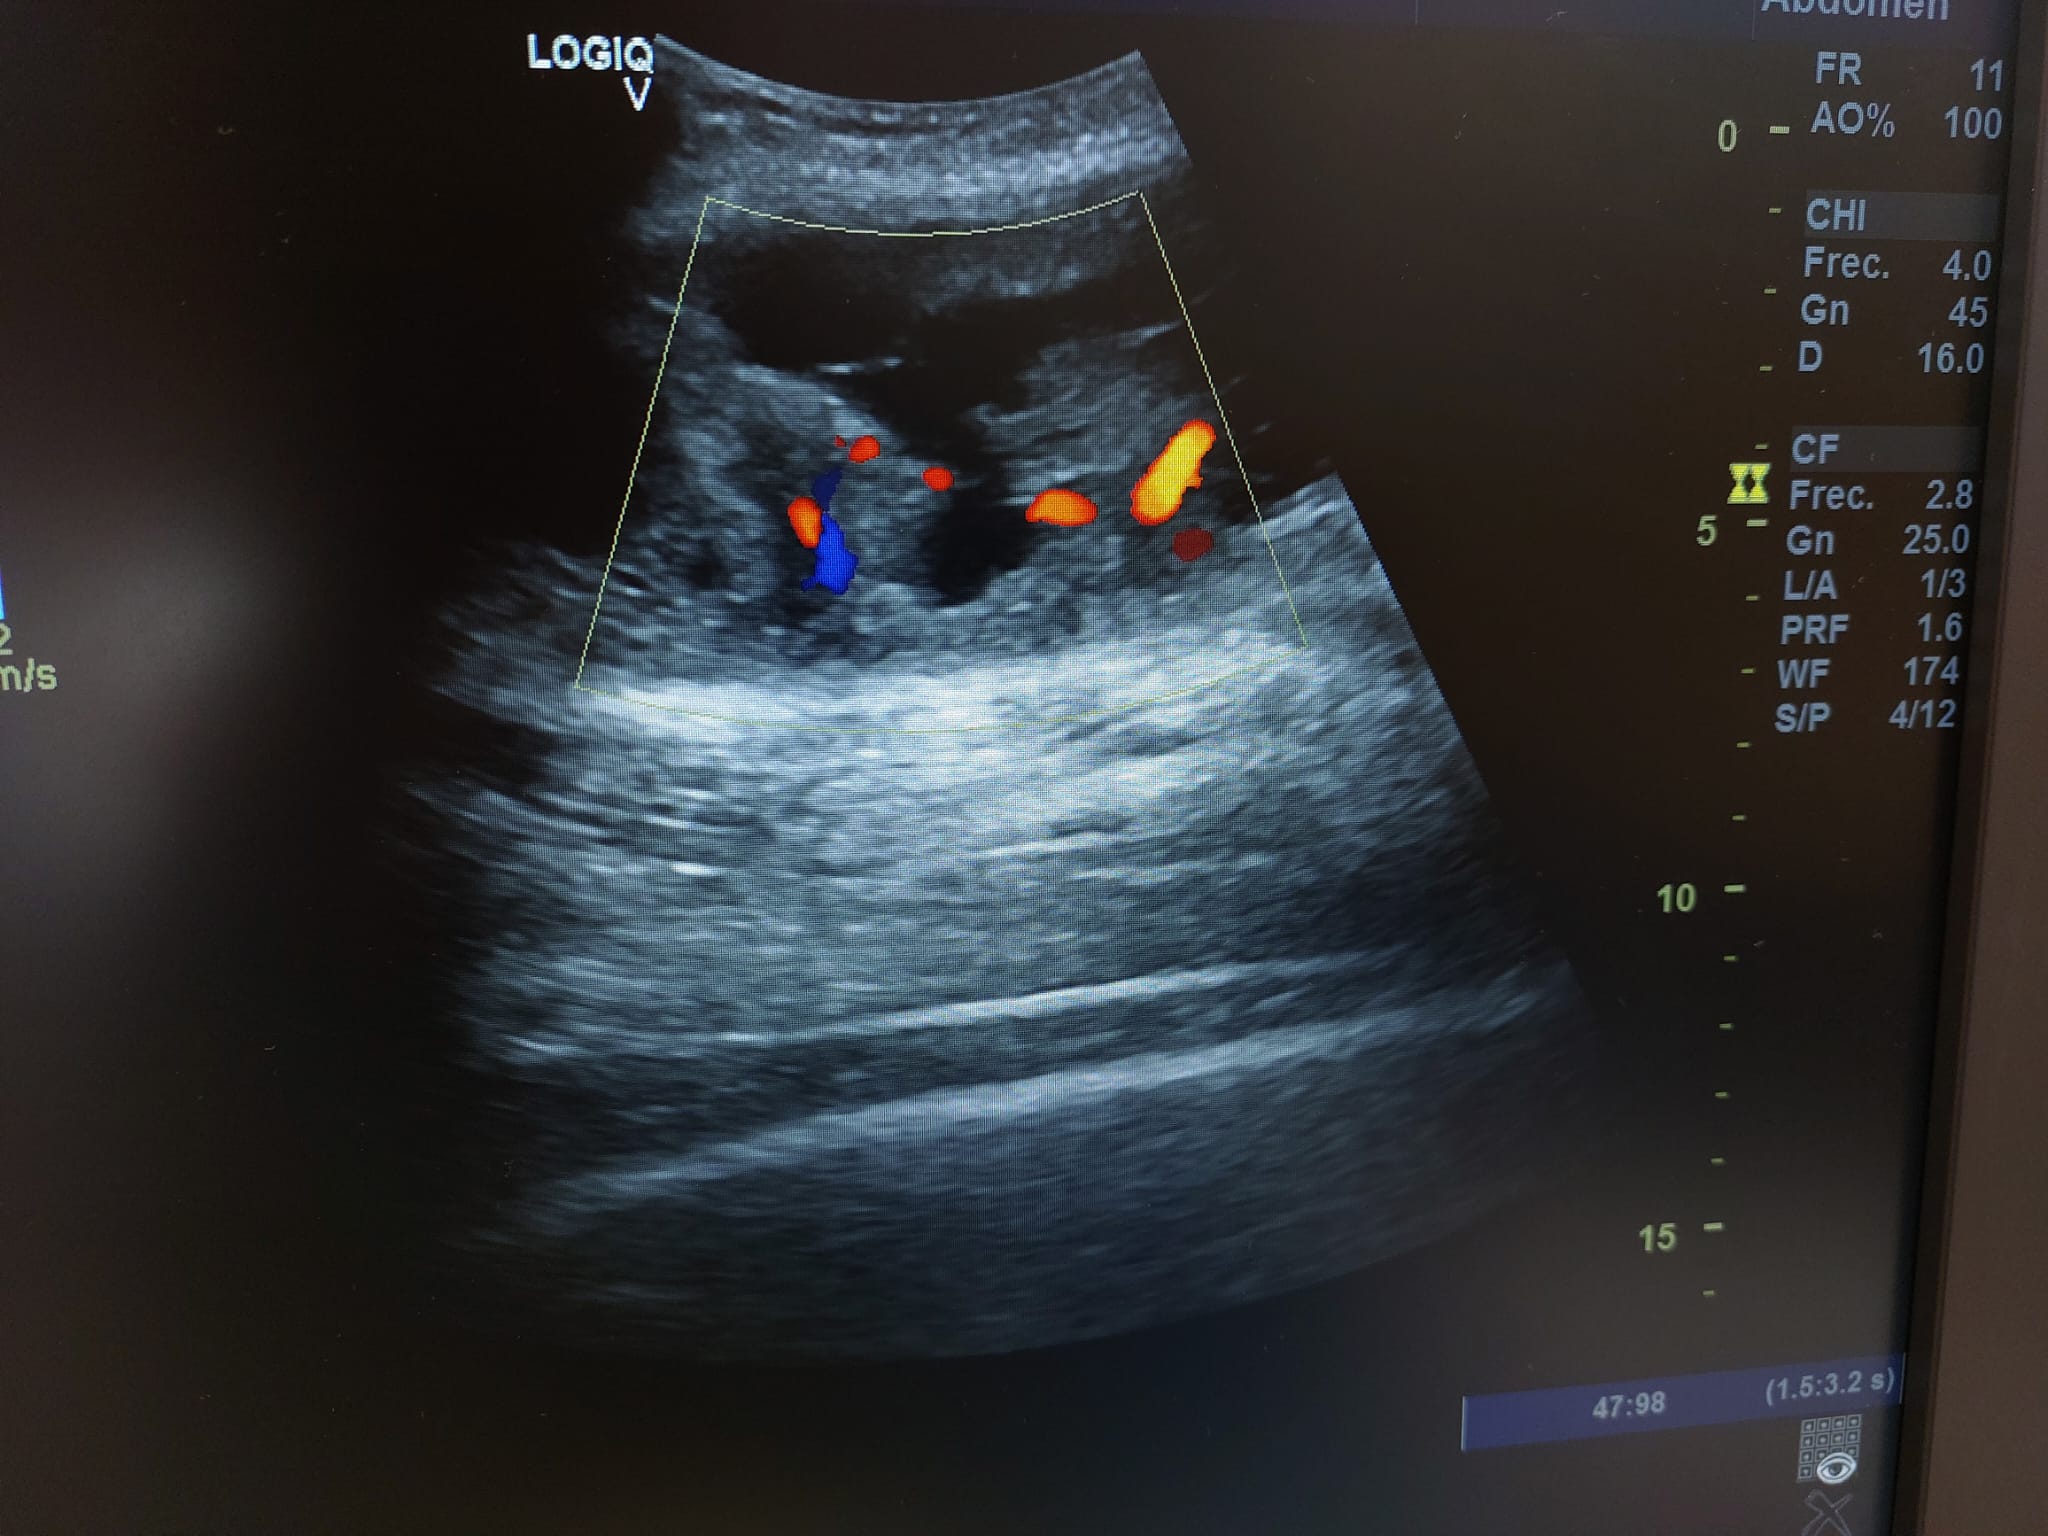

En el seguimiento se observa evolución tórpida sin mejoría clínica y en la ecografía de control se observa aumento notable de tamaño respecto al previo, estructura heterogénea de imagen anecoica con septos internos. Se aprecia edema intramuscular perilesional y captación al activar el Doppler. Se plantea la posibilidad de un hematoma sobreinfectado o, debido a su importante crecimiento, una probable etiología neoplásica. Tras hallazgos descritos en consulta, COT solicita de forma urgente la realización de RNM y biopsia de la lesión. Posteriormente, el resultado de las pruebas complementarias confirman diagnóstico de sarcoma histiocítico.